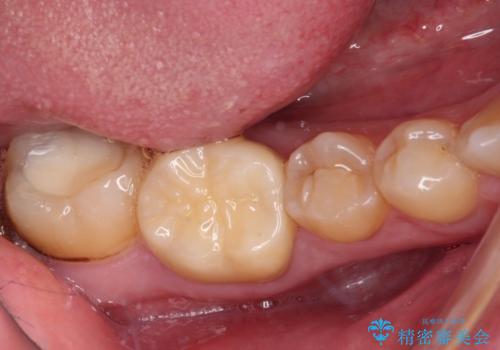

- 左右下顎の奥歯に違和感を感じるとのことで来院された患者様です。

最近ものが挟まりやすくなったり、冷たいものがしみるようになったりと言った症状があり、診査したところ、歯質の欠損や不適修復物などが認められました。

精度の高いセラミックインレーによる修復治療が第一選択となりますが、一方の歯は元々修復物が大きく、咬合力の強い方であったので、セラミッククラウンによる補綴治療を行うこととしました。